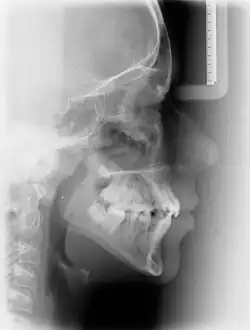

Vor jeder kieferorthopädischen Behandlung muss eine ausführliche Diagnostik erfolgen. Diese besteht aus einer ausführlichen allgemein- und zahnärztlichen Anamnese sowie der ätiologischen Beurteilung der Patientensituation. Anschließend folgt die klinische Untersuchung, eine Funktionsanalyse, Modellanalyse und eine fernröntgenologische Untersuchung. Mit Hilfe dieser Untersuchung wird die Kieferrelation, die Lagebeziehung zwischen dem Oberkiefer und Unterkiefer, dargestellt. Gleichzeitig werden die dentoalveolären Befunde erhoben und das Dentitionsstadium festgestellt.[4]